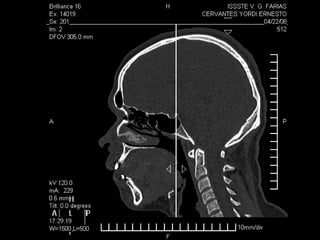

Tomografía computarizada

De seno maxilar corte sagital.

Area de implantación

Dentaria.

Material osteoconductor

para elevar el piso antral

Nuevo piso del seno y su

margen de seguridad para

contener el implante

Tomografía computarizada De senomaxilar corte sagital. Area de implantación Dentaria.

Nuevo piso delseno y su margen de seguridad para contener el implante dentario